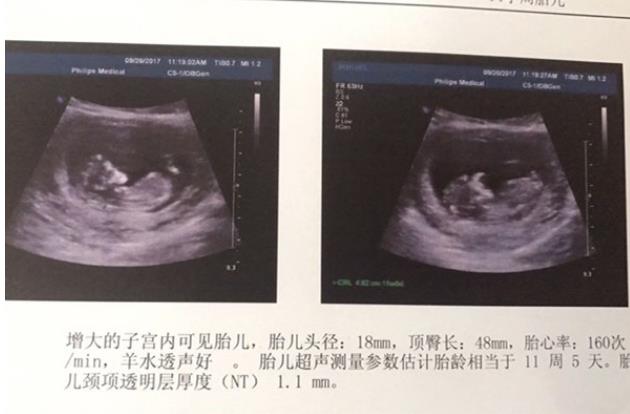

孕婦做二維彩超需要空腹嗎?這些事你得知道